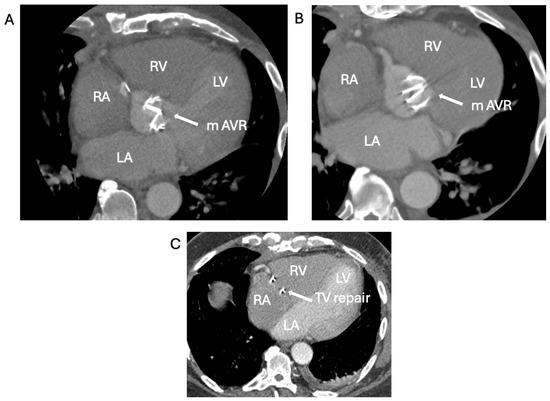

2.3. The Saga of Relapsing IE of the Prosthetic Mitral Valve Causing Structural Valve Degeneration and Transcutaneous MViV Prosthesis